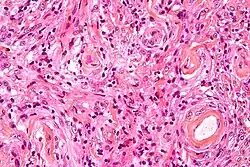

Histopathology of a typical WHO grade 1 meningioma, H&E stain. It is of the meningothelial histologic type, which is the most common meningioma type. It shows its typical findings:

- A woven architectural pattern

- Psammoma bodies (spheroid calcifications)

- Syncytial cells (having indistinct cell membranes) with eosinophilic (pink) cytoplasms

- Round uniform nuclei

- Whorls (concentric cell arrangements)[16]